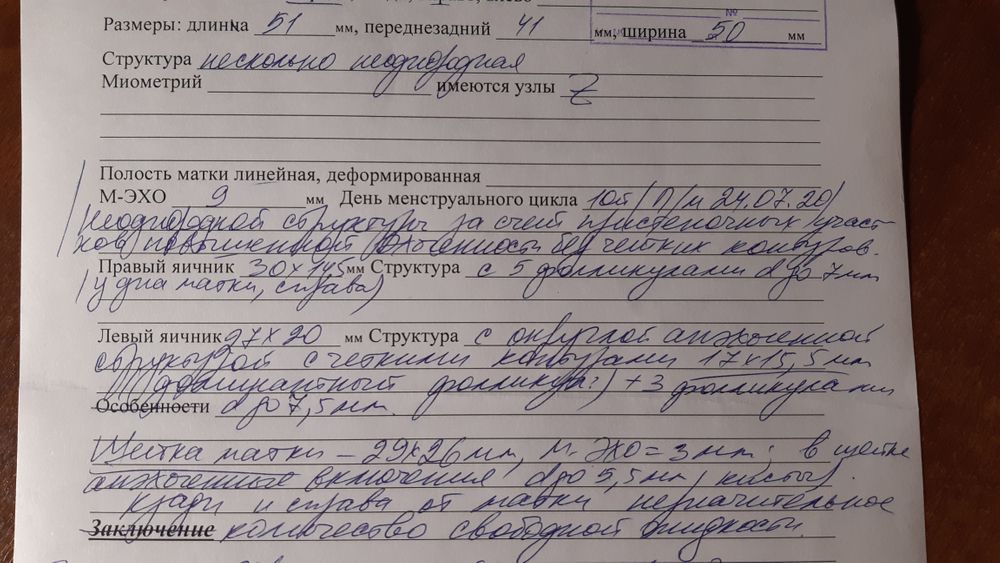

Каждый месяц после мес я хожу на узи, слежу за эндометрием, так как после вакуума в декабре он был очень неоднородный, хэ по узи под?, было лечение. Сегодня была на узи. Картинка м эхо лучше, это очень радует. Крайний месяц был уже без терапии. После долгой спячки ля выдал таки доминантный фолликул (О решила отслеживать дальше несколько циклов для себя в купе с тестами). Но есть и моменты не очень радующие:

-эндик по структуре как во второй фазе, со слов узиста.(у меня бывают иногда циклы в 24-26дней, она предположила, чтот цикл будет именно таким-короче положенного).

-наличие свободной жидкости. Это встречается уже не впервый раз. Ее быть не должно в норме(((

-маловато фолликулов сказала узист(((.

Фото эндика и ля прикладываю.